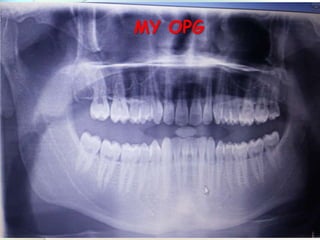

MY OPG

Max.3rd molars Man. 3rd molars Max. & Man.